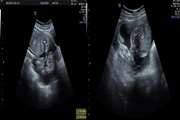

Benign hepatic schwannoma in a patient with chronic hepatitis B infection: A case report 1403/12/26 - 13:43